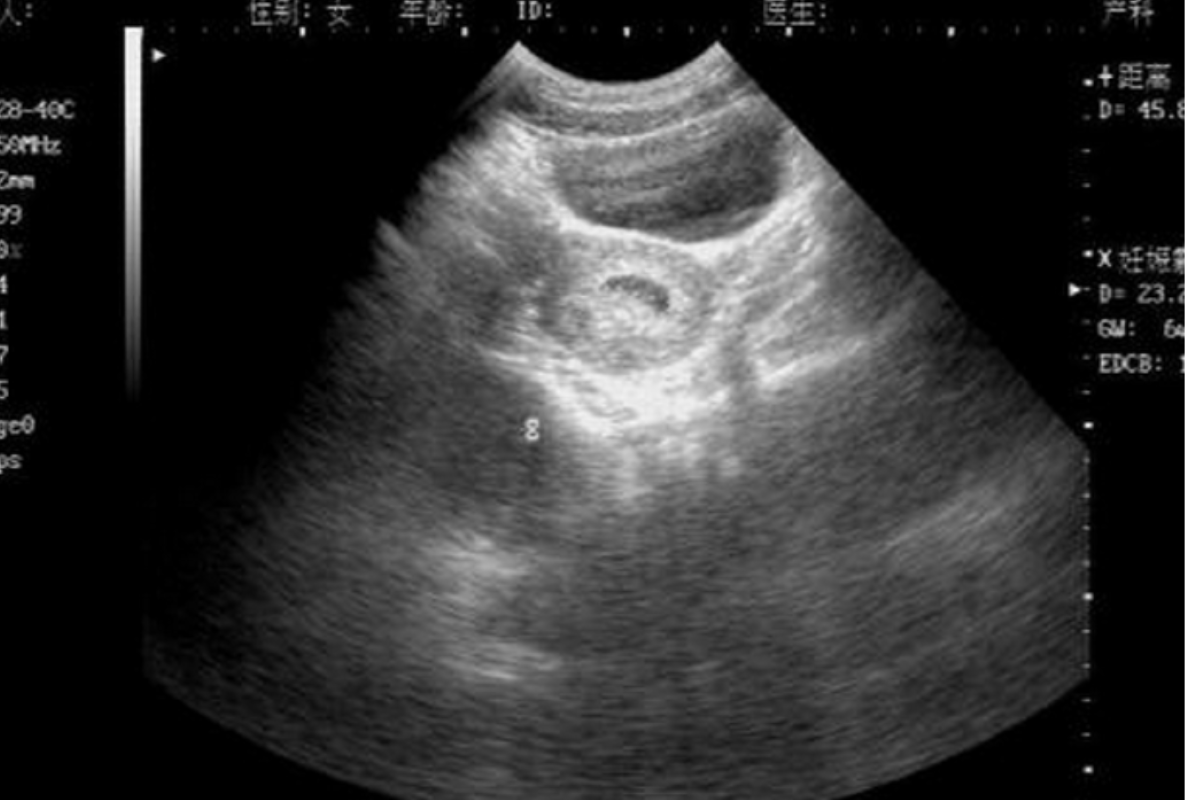

2011年2月21日,在遂宁市第三人民医院里,廖国军正指着妻子B超报告上“宫内单活胎”的字样不停询问着医生。

2011年5月3日,因为肚子再次出现明显的疼痛,包桥英急忙将外出买菜的廖国军叫了回来。两人一同到遂宁市妇幼保健院做了B超,可这次的检查结果却显示他们的孩子是连体双胎,这与两个多月前遂宁市第三人民医院给出的结果大相径庭。

检查报告一出来,廖国军急忙上前,可机器不会说谎,冷冰冰的检查报告上面依然是“连体双胎”的字样,并且下面还附有一行字:已错过产前诊断检查最佳时期。

廖国军还有些懵,突然想起报告上这个“已错过产前诊断检查最佳时期”是什么意思。医生解释道,这是指胎儿在18周以后就能检查出是否存在畸形,他们错过了这个时间。可廖国军心里清楚,上一次去遂宁市第三人民医院检查时都已经6个月了,可为什么没有检查出来呢?